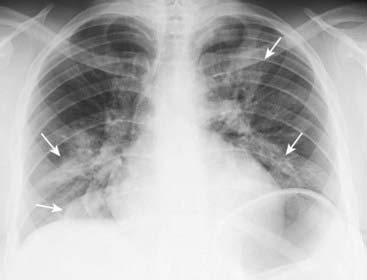

image image

Figure 7-12 Composite appearances of lobar pneumonias.

A, Right upper lobe. The disease obscures (silhouettes) the ascending aorta. Where it abuts the minor fissure, it produces a sharp margin (white arrow). B, Right middle lobe. The disease silhouettes the right heart border (solid black arrow). Where it abuts the minor fissure, it produces a sharp margin (solid white arrow). C, Right lower lobe. The disease silhouettes the right hemidiaphragm (solid black arrow). It spares the right heart border (dotted black arrow). D, Left upper lobe. The disease is poorly marginated (solid white arrow) and obscures the aortic knob (solid black arrow). E, Lingula. The disease silhouettes the left heart border (solid black arrow) but spares the left hemidiaphragm (dotted black arrow). F, Left lower lobe. The disease obscures the left hemidiaphragm (dotted black arrow) but spares the left heart border (solid black arrow).